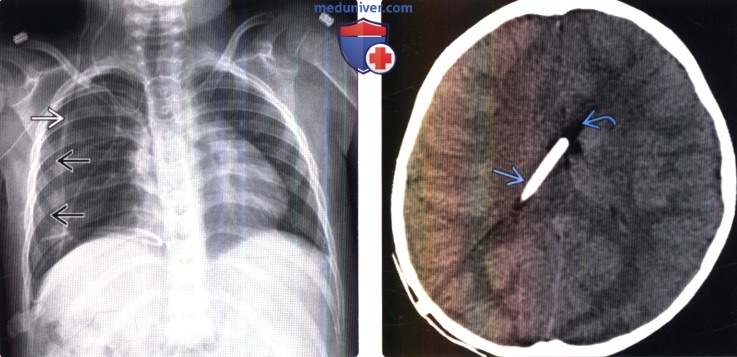

Вентрикуло-перитонеальный шунт: Показания и применение

Раздел: Фотоальбом решений